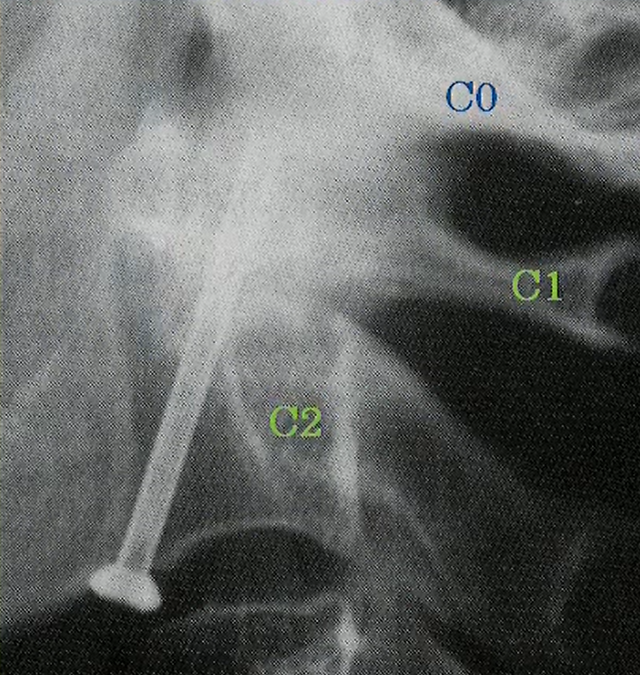

①歯突起骨折

歯突起骨折には3分類あります。

(右のイラスト参照)

Ⅰ型 歯突起の先端が骨折するタイプ(きわめて稀)

Ⅱ型 歯突起の根元が骨折するタイプ(最も多い)

Ⅲ型 Ⅱ型よりも根元(椎体部)まで骨折するタイプ

では歯突起骨折になった場合にどのような治療をするのでしょうか。

Ⅰ型の場合はさほど大きな障害になることが無いため経過観察が基本です。

ⅡとⅢ型はギブスで固定して経過観察が基本です。

但し、うまく癒合しない場合は歯突起固定術が不可欠になります。(右の画像)

歯突起固定術が必要なケースはⅡ型が多くあります。